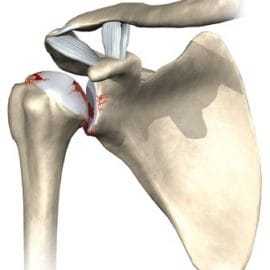

При повреждении плеча часто травмируется хрящевая губа. В итоге теряется стабильность сустава. Её потеря также связана с дефектом костного компонента суставной впадины лопатки (гленоида).

Повреждение манжеты

Ротаторная манжета образована четырьмя мышцами и их сухожилиями. Они необходимы для стабилизации сустава или вращения кости. При повреждении манжеты часто используются артроскопические операции.